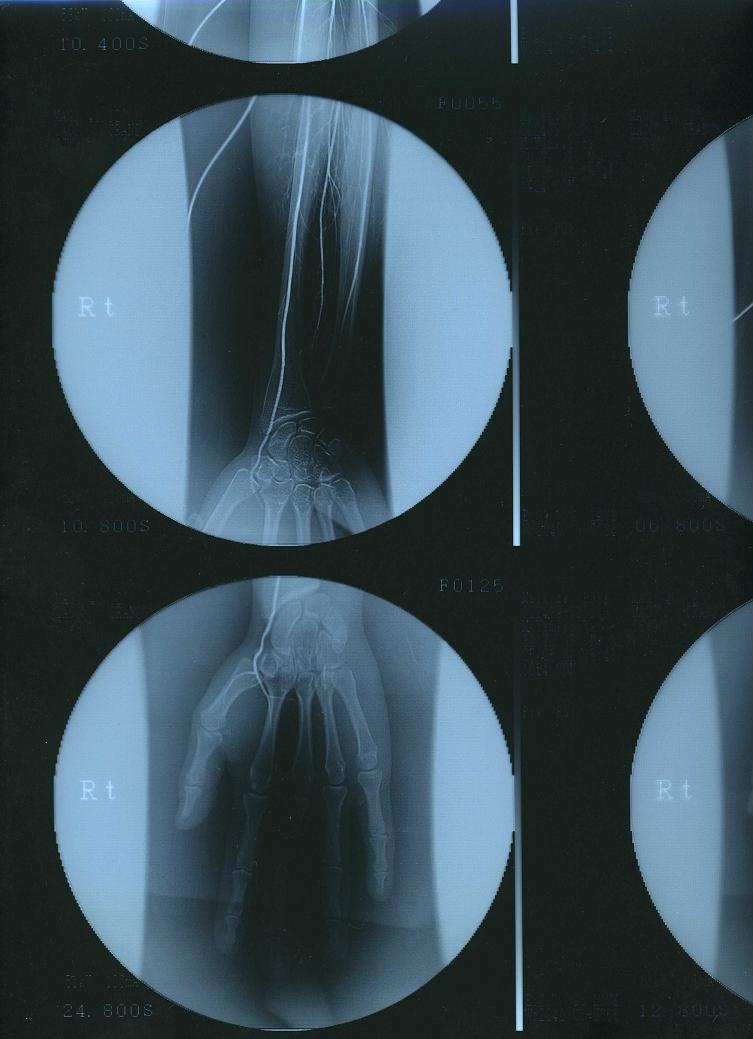

そして、初めてカミングアウトする病気は…病名『ビュルガー病』

私の場合、どうも突然変異の生まれつきだったみたい。

で、顕著に症状が酷く出たのが28歳の時…

この病気は9割方、男性がかかる病気なので、女性と老人が疑わしい時は男性より厳しい検査をします。

薬と冬場の血管拡張の点滴でなんとか現状維持してるんだけど…

血液が指の先に十分に流れないので…

爪の発育がとても悪く、脆い歪な爪をしています。

本来なら強く固い親指の爪は人差し指の爪で簡単に削ったり、破ったりできます。